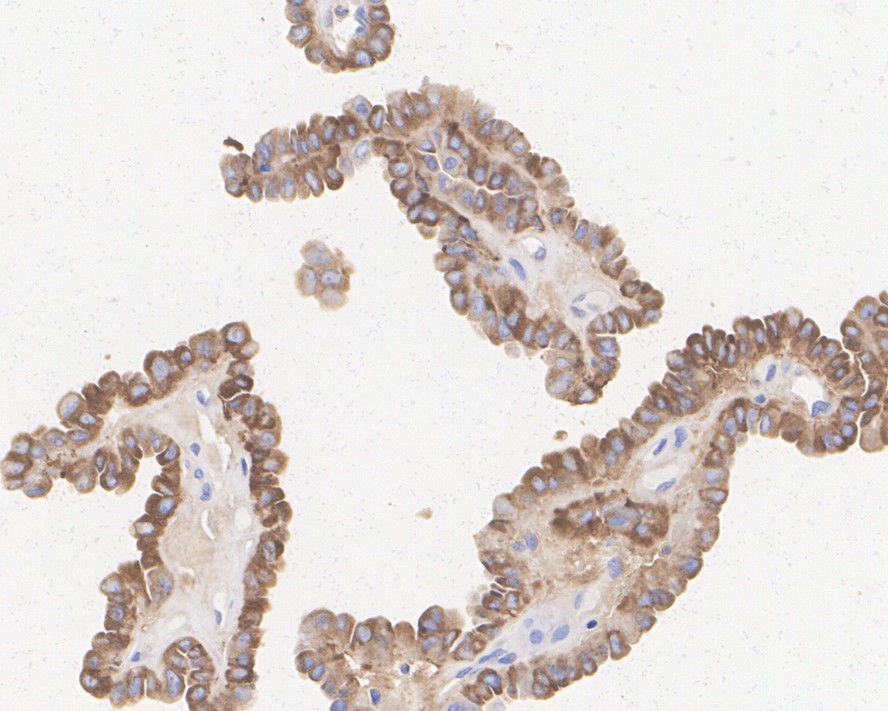

Thyroglobulin Recombinant Rabbit Monoclonal Antibody [JE47-61]

IHC-P